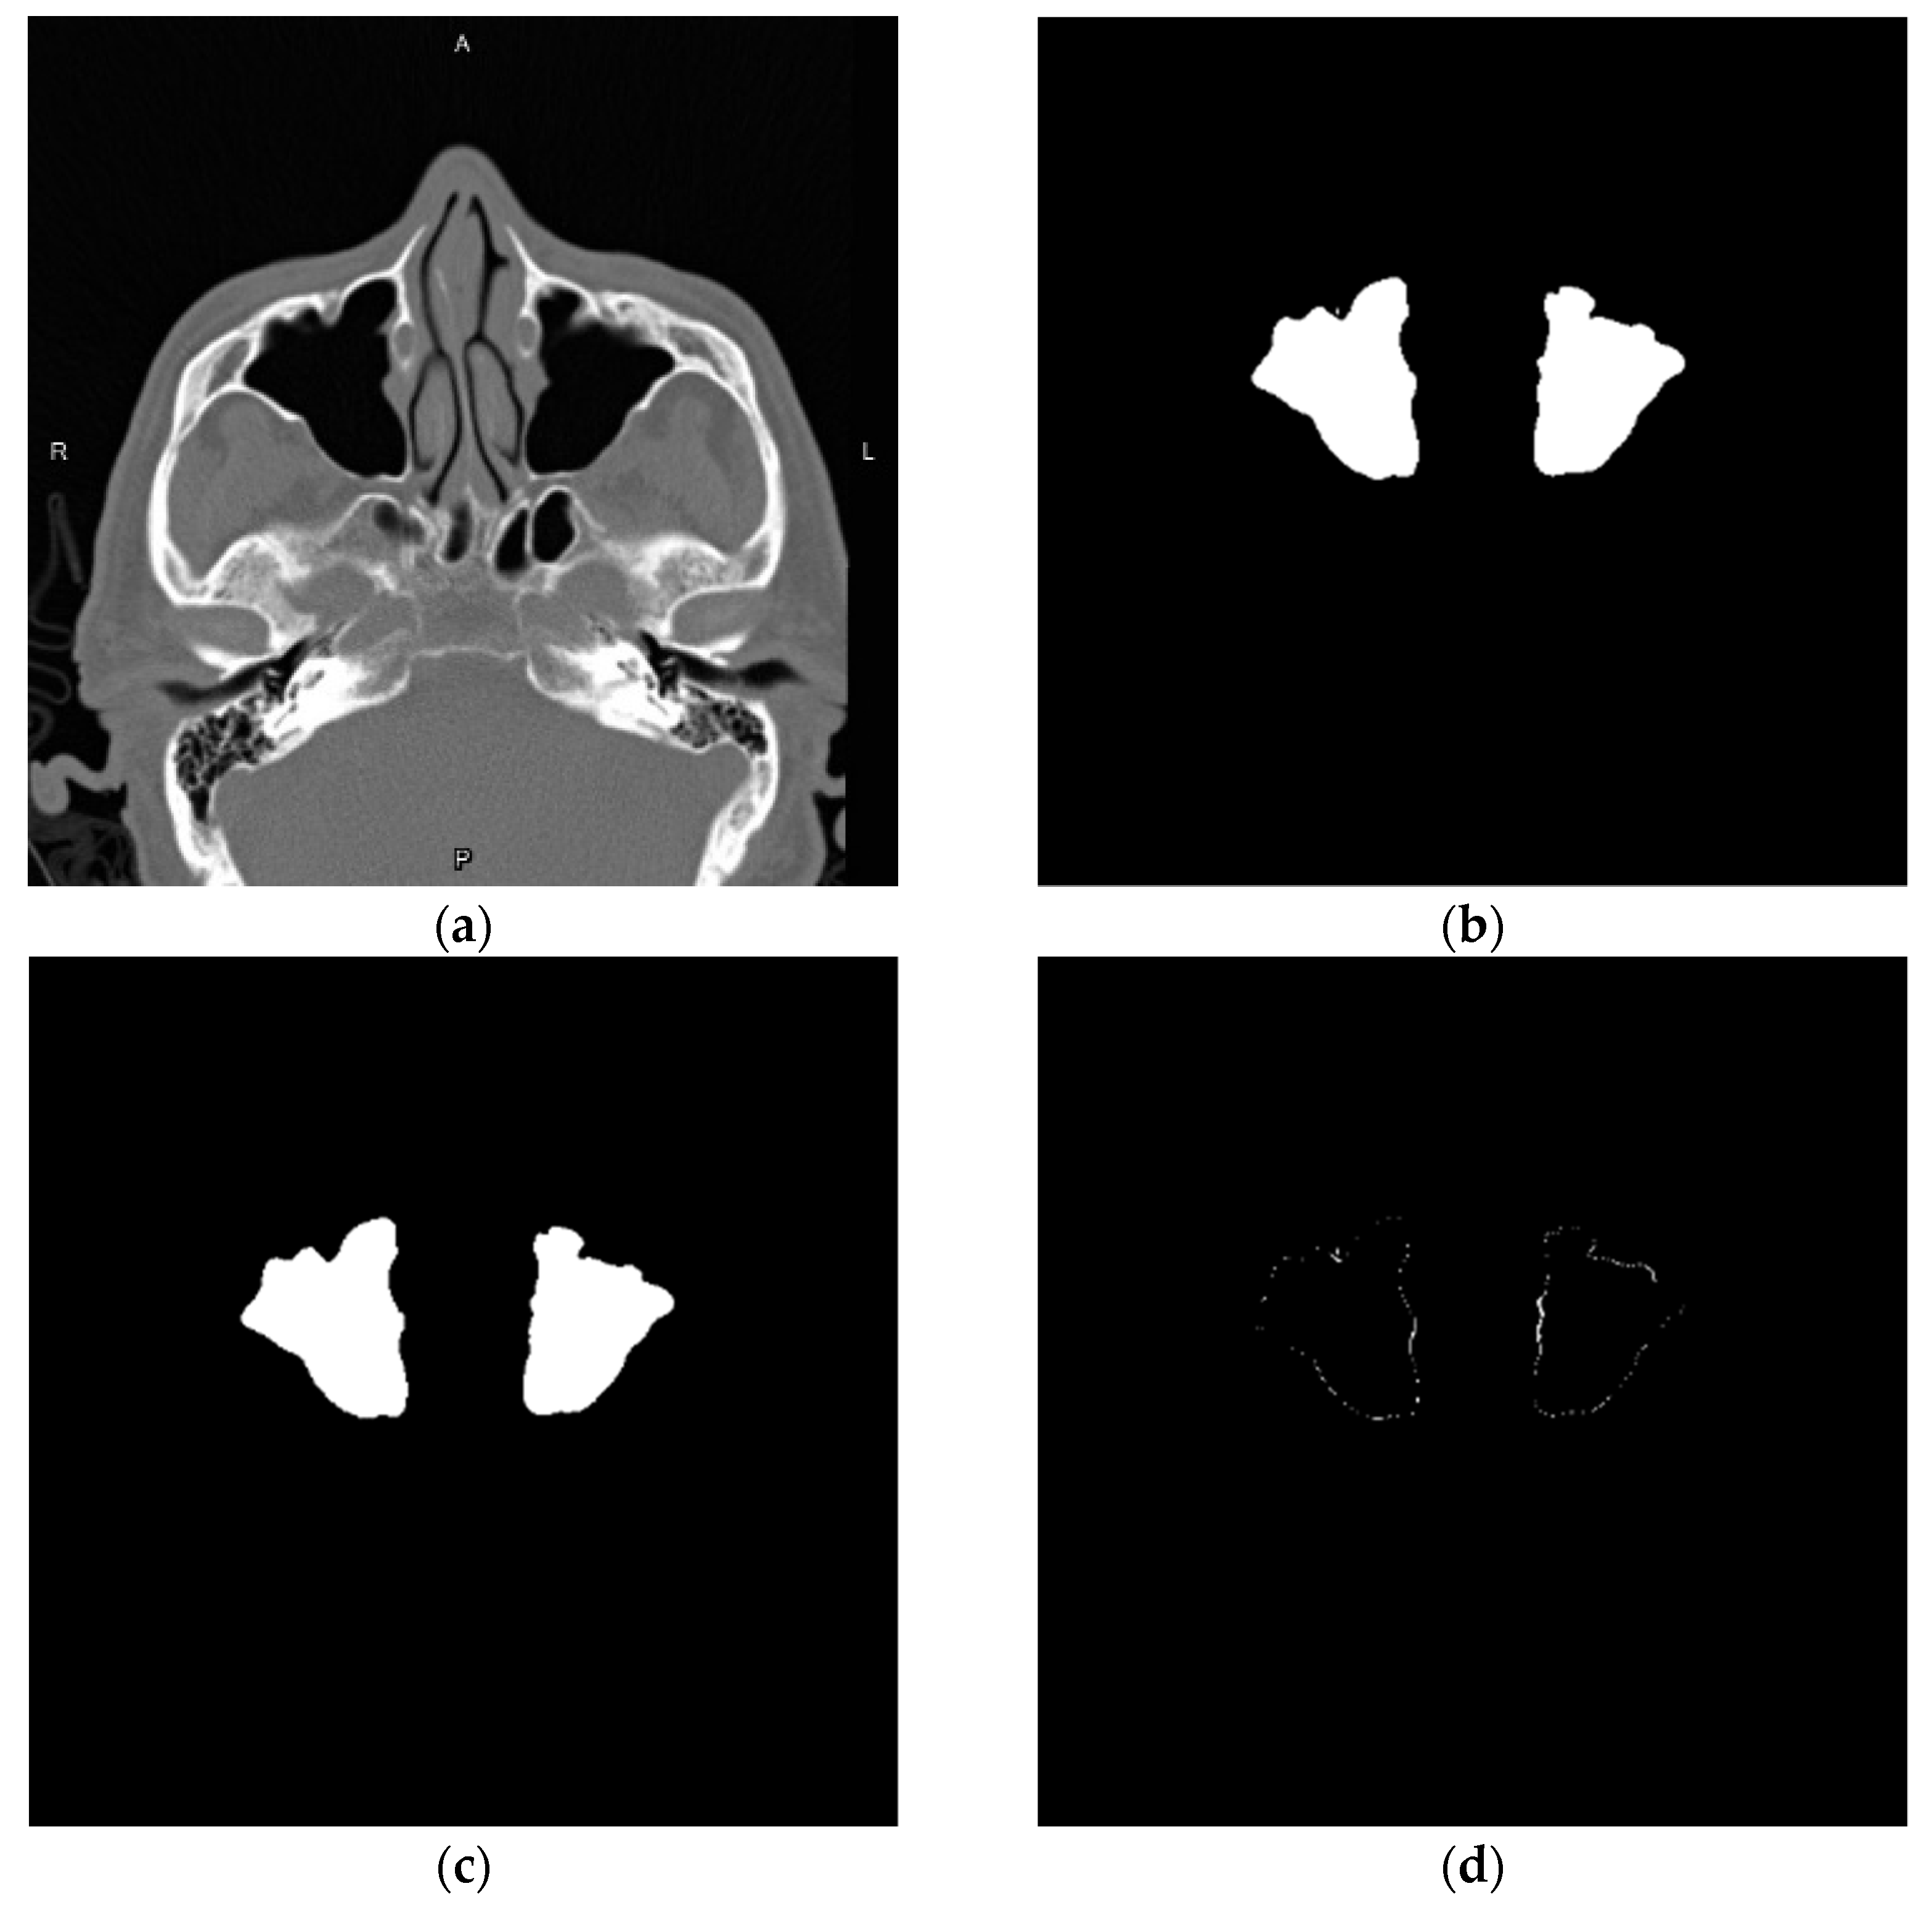

3.1. Image Data Augmentation

3.1.1. Gaussian Blur